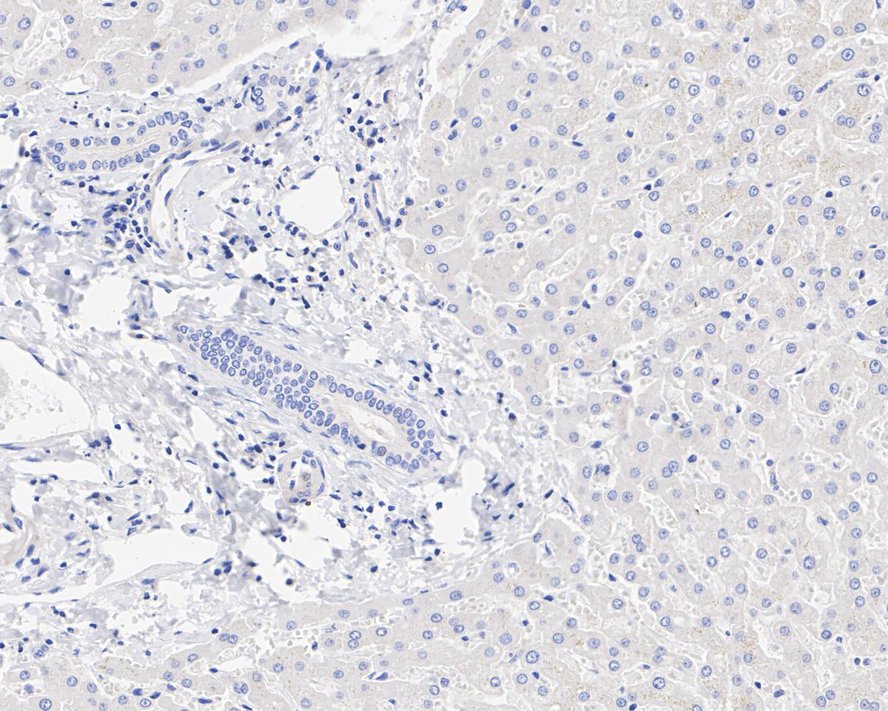

Immunohistochemical analysis of paraffin-embedded human liver tissue (negative) with Rabbit anti-MUC16 antibody (HA721217) at 1/2,000 dilution.

The section was pre-treated using heat mediated antigen retrieval with Tris-EDTA buffer (pH 9.0) for 20 minutes. The tissues were blocked in 1% BSA for 20 minutes at room temperature, washed with ddH2O and PBS, and then probed with the primary antibody (HA721217) at 1/2,000 dilution for 1 hour at room temperature. The detection was performed using an HRP conjugated compact polymer system. DAB was used as the chromogen. Tissues were counterstained with hematoxylin and mounted with DPX.